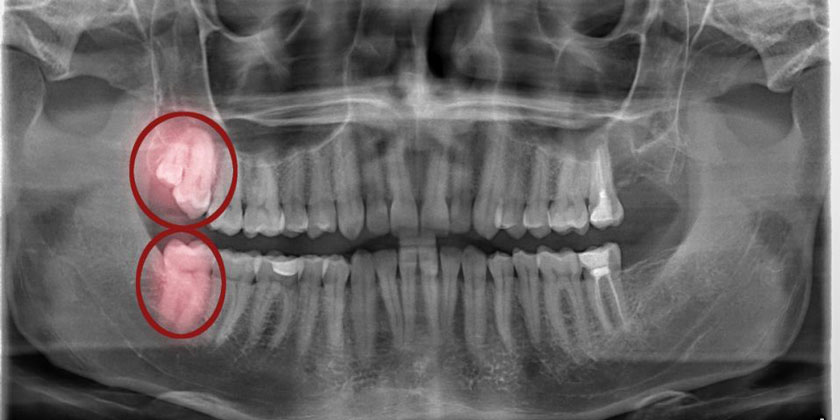

2. Mọc răng khôn

Đau răng ở người trưởng thành có thể xuất phát từ nguyên nhân mọc răng khôn. Răng khôn thường mọc trong giai đoạn 17-25 tuổi, quá trình mọc thường kèm theo nhiều triệu chứng như đau nhức, hành sốt… Đặc biệt răng khôn hay mọc lệch, mọc ngang, mọc ngầm, bị sâu, bị viêm nướu trùm… gây ra những cơn đau răng dữ dội, khó há miệng, viêm nhiễm...

Mọc răng khôn thường gây đau nhức, viêm nhiễm